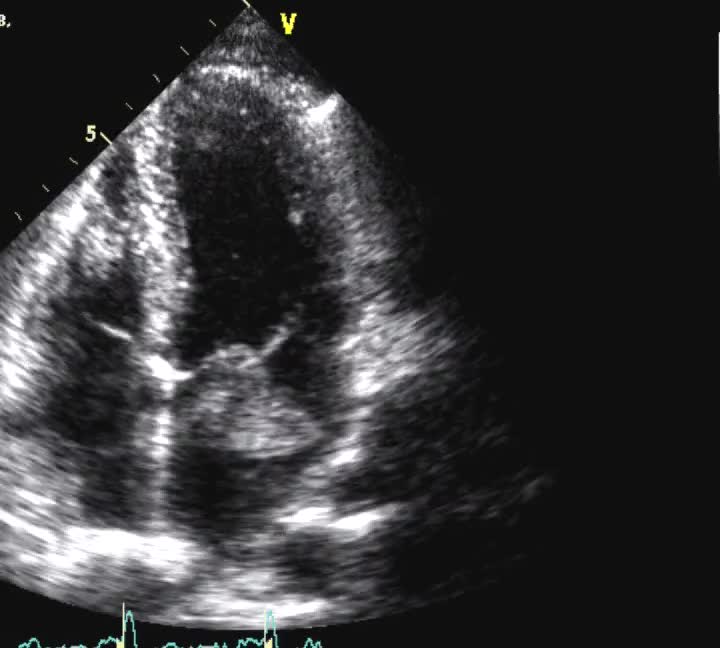

Titolo:

Autore: